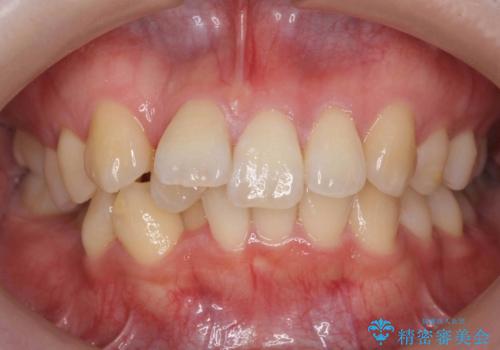

【モニター】左右のクロスバイトをインビザラインできれいに改善